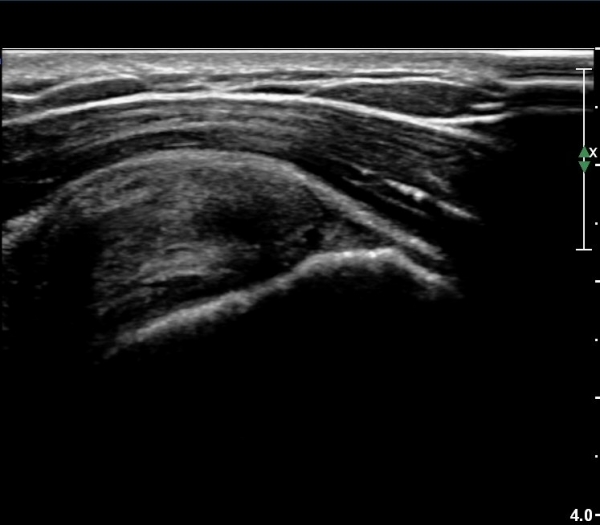

ÀÌµÎ¹Ú±Ù°Ç ÀåµÎ Ⱦ´Ü¸é°Ë»ç¿¡¼­ °ÇÁÖÀ§ ¼ö¾×Àú·ù°¡ °üÂûµÈ´Ù(»çÁø 3).